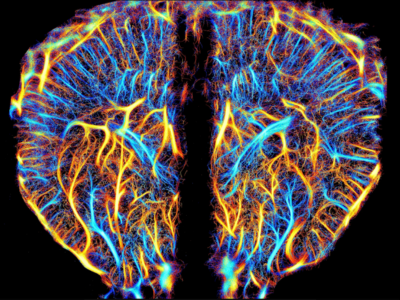

No 1 | Planifier la résection d’une tumeur cérébrale à l’aide des circuits cérébraux